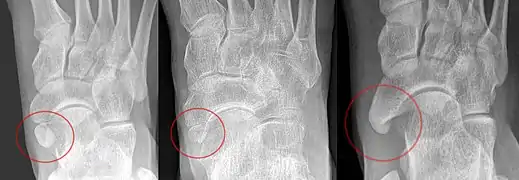

Radiological images

From left to right: Type 1, 2 and 3